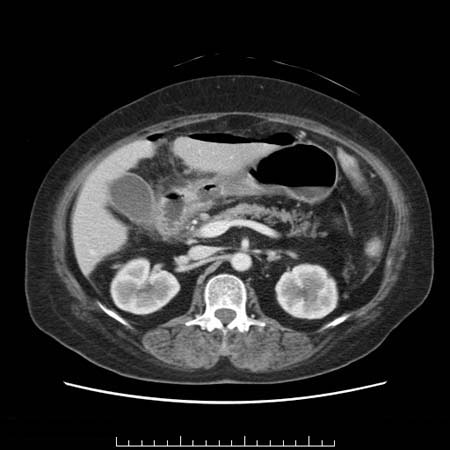

胃潰瘍穿孔のCT所見

・遊離ガス:被覆穿孔では遊離ガスは認めない

・胃壁の陥凹と周辺の壁肥厚

・周囲脂肪織不整

・腹水

*正常の胃壁の厚さ:4mm~1cm

*厚さ(数値)のみでなく造影効果や壁の性状(層構造)にも注目する

胃潰瘍穿孔の治療の原則は手術(開腹、腹腔鏡)であるが、保存的治療を選択できる場合もある。いずれにしろ早急に専門医と相談する。